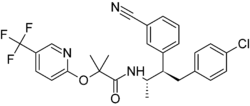

| Formula | C27H25ClF3N3O2 |

| Molar mass | 515.96 g·mol−1 |

Taranabant (codenamed MK-0364) is a cannabinoid receptor type 1 (CB1) inverse agonist that was investigated as a potential treatment for obesity due to its anorectic effects.[1][2] It was discovered by Merck & Co.

- ↑ Fong TM, Guan XM, Marsh DJ, Shen CP, Stribling DS, Rosko KM, et al. (Jun 2007). "Antiobesity efficacy of a novel cannabinoid-1 receptor inverse agonist, N-[(1S,2S)-3-(4-chlorophenyl)-2-(3-cyanophenyl)-1-methylpropyl]-2-methyl-2-5-(trifluoromethyl)pyridin-2-yl]oxy]propanamide (MK-0364), in rodents". Journal of Pharmacology and Experimental Therapeutics. 321 (3): 1013–22. doi:10.1124/jpet.106.118737. PMID 17327489. S2CID 20001781.